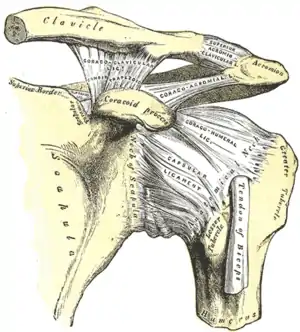

La scapula s'articule avec la clavicule au niveau de l'acromion. Cette jonction entre ces deux os est connue sous le terme d'articulation acromio-claviculaire[5] qui dispose également de trois degrés de liberté. Cette articulation est fixée par quatre ligaments[6].

En dessous de l'acromion de la scapula se situe une cavité appelée « cavité glénoïdale » qui reçoit la tête de l'humérus. Cette jonction constituée de la cavité glénoïdale de la scapula et la tête de l'humérus se nomme articulation gléno-humérale (ou scapulo-humérale)[5].

- Articulation acromio-claviculaire :

- le ligament coraco-claviculaire reliant la clavicule au processus coracoïde de la scapula,

- le ligament conoïde allant de la base du processus coronoïde, en éventail, jusqu'au tubercule conoïde de la clavicule,

- le ligament trapézoïde qui va du bord supérieur du processus coaracoïde jusqu'à la ligne trapézoïde de la clavicule,

- le ligament acromio-claviculaire dont la fonction est de renforcer la capsule articulaire au niveau de sa partie supérieure..

- Articulation gléno-humérale :

- le ligament coraco-acromial qui relie le processus coracoïde à l'acromion formant une voûte fibreuse au-dessus de l'articulation,

- le ligament coraco-huméral qui relie le processus coracoïde aux tubercules majeur et mineur de l'humérus tout en renforçcant la partie supérieure de la capsule articulaire.

- les ligaments gléno-huméraux qui constituent des fibres venant renforcer la partie antérieure de la capsule articulaire.